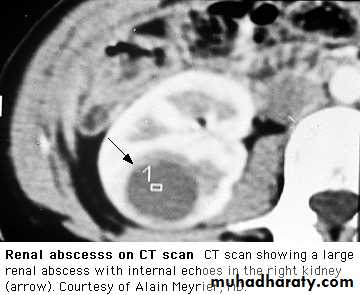

Perinephric abscess marked pain and tenderness and bulging of the loin , extremely ill, with fever, leucocytosis and positive blood cultures. Urinary symptoms are absent, and urine contains neither pus cells nor organisms.

KUB Radio oapquestone , emphesemaRenal ultrasound or CT To identify obstruction, cysts, calculi perinephric collection.